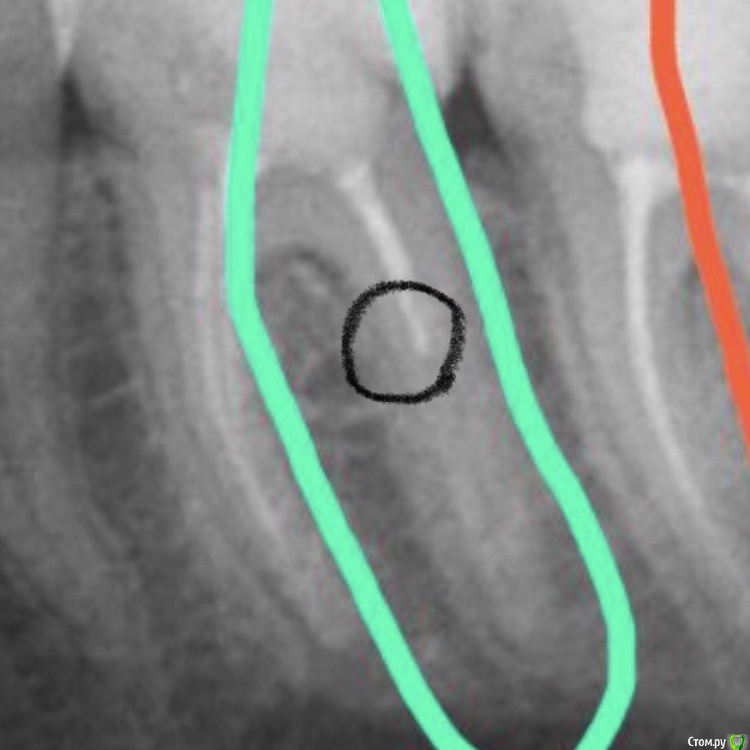

Marialalala Опубликовано 12 декабря, 2019 Поделиться Опубликовано 12 декабря, 2019 Здравствуйте, такая ситуация. Обратилась к стоматологу с жалобами на нижние 7-ку и 6-ку (к слову, у меня всегда страдает пришей-ка, на 7-ее уже стояла большая пломба плюшка на пришейке, я уже понимала, что именно этот зуб двери реакцию на холодное/горячее, поэтому велика вероятность чистки каналов, на соседней 6-ее начал уже образовываться тоже пришеечный кариес, но невооруженным взглядом видно (у меня их было много), что это просто кариес, причём не глубокий точно. Я сделала на всякий панорамный снимок перед походом, в глаза бросилось, что в 6-ке, на той стороне, где соприкасается с 7-ой, есть приличный кариес, но плюшку на 7 и пришейку на 6 по снимку (по крайне мере мне) видно не было. Я пришла к врачу, он начинает с 7-ки, чистит плюшку, ну собственно говорил, что лечим каналы, отсюда и неприятные ощущения, с которыми я обратилась, ну ок, пролечили, потом записалась уже на след раз на лечение пришейки в 6 (я не помню показывала ли панораму врачу, точнее я наверняка предложила, он сказал не надо, но в голове держу, что видела я кариес приличный ещё между 6 и 7, но ему не говорю, не умничаю, всё-таки наверняка сам увидит (причём дома когда я открывала рот, то этот участок был более темный, чем остальной зуб, поэтому была уверена, что врач то точно увидит и как раз пролечит пришейку и эту вторую поверхность зуба). Врач пролечил пришейку, вторую часть не тронул, я прихожу опять к нему, ведь реакция на холод опять бывает (ну логично же, когда там кусок кариеса приличного остался), пришла, врач сказал, ну если не прошло, значит лечим каналы, ок, подумала я, придётся из-за этого кариеса лечить каналы, видимо врач понял, что там все глубого пошло. Но какого было мое удивление, когда я чувствую, что врач открывает доступ к каналам по середине, и чистит их, ну думаю тот кариес то он тоже убрал, но нет!! Мне пролечили каналы, к слову, снимок не делали! И у меня остался этот кариес, пришла в след раз ещё раз и показываю фото ему первое, мол вот тут же затемнение такое, это не кариес разве? Врач отвечает, что это просто затемнение и ничего не трогает. Через месяц-второй эта часть зуба, где кариес успешно откололась, я пришла к нему, он прочистил и поставил пломбу, потом отвалилась пришейка маленькая, но я уже не пошла к нему, а пошла на лечение в другую клинику (через 3-4 месяца после лечения двух зубов, сделав ещё один панорамный снимок, врач говорит, что один из каналов в 6-ее не пройдёте до конца, перелечивает, делает контрольный прицельный снимок, на который попадает 6-ка и 7-ка и говорит мне о том, что в 6-ке возможно кусочек инструмента (обведено чёрным), канал не получается пройти, ну либо там просто такой участок препарата крепкого, который чтобы это не было из двух надо проходить, благо воспаление в 6-ее есть, но не сильное, но по снимку попавшая 7-ка (фото нет прицельных снимков уже у этого врача) видно, что там уже киста есть. В общем оба зуба перелечивать, если все воспаление уйдёт, то ставим коронку, если вдруг нет, то есть риск удаления. В итоге каждый зуб при лучшем раскладе встанет мне в 25 тысяч, то есть я заплачу минимум 50 тысяч из-за некачественного лечения первого врача. Как мне быть? Оставить все как есть или писать досудебную претензию? (Друзья против того, чтобы я оставляла это безнаказанным) Ссылка на комментарий